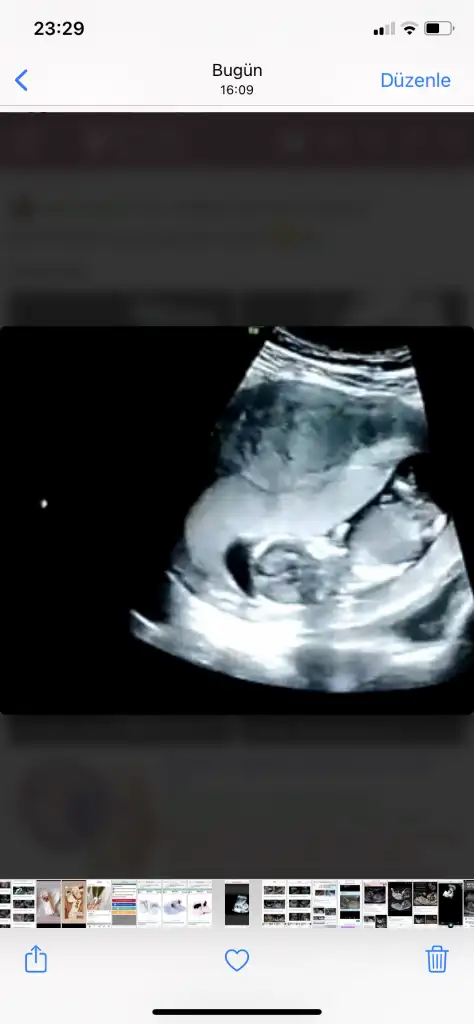

Merhaba canım ilk bebegimi doğru tahmin etmiştim ikinciye hamile kaldım şimdilik bı tane resim var telefonumda ekrandan çekmiştim çıktısı yanımda değil bı bakabilirmisin cinsiyeti acaba ne.9+5burda.

Eklentiler

• IMG_20210326_092231.webp

IMG_20210326_092231.webp

53,2 KB · Görüntüleme: 77